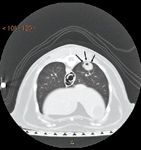

The correlation between tracheobronchial lymph node involvement and shorter remission times stresses the importance of computed tomography (CT) in the diagnostic work-up of dogs with primary lung tumors.2,3,7 In a study of 14 dogs with primary lung tumors, researchers evaluated the accuracy of CT vs. thoracic radiography in determining tracheobronchial lymph node involvement. CT had greater sensitivity and an increased predictive value for detecting tracheobronchial lymph node metastasis. The overall accuracy of CT in detecting lymph node metastasis was 93% compared with 57% for thoracic radiographs. False negative diagnoses made with thoracic radiographs may be attributable to the fact that the lymph nodes were still small (< 15 mm) or may have been obscured by surrounding structures, including the primary tumor itself.7

The sensitivity of CT is also superior in imaging metastatic pulmonary nodules when compared with thoracic radiography. CT was found to detect not only smaller pulmonary nodules (1 mm, compared with the minimum nodule size of 7 to 9 mm detectable on radiographs) but also a greater number of total nodules at more precise lobar locations (Figure 5). Radiographs failed to detect 90% of nodules detected on CT.39 These recent studies suggest that thoracic CT is rapidly becoming a mandatory diagnostic test performed before surgical removal of any primary tumor with potential pulmonary metastasis.

5. A thoracic computed tomographic image from a 12-year-old castrated male domestic shorthaired cat presented for evaluation of inappetence and weight loss. A cavitated mass (arrows) is identified in the periphery of the right caudal lung lobe. The mass was removed with thoracoscopic lung lobectomy, and the histologic examination results revealed a well-differentiated adenocarcinoma. (Photograph courtesy of Dr. Kristen O Dell-Anderson.)